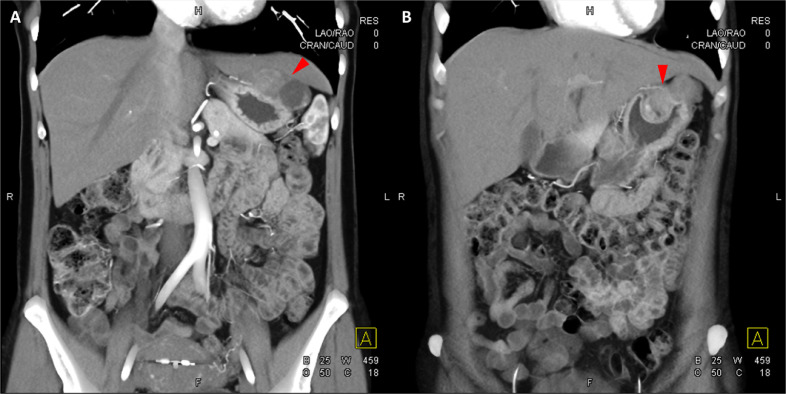

Fig. 4

圖 4: 胃腸道間質(zhì)瘤的三維表示。 (A 和 B)胃腸道間質(zhì)瘤在動(dòng)脈期和冠狀面的 3D 可視化提供了進(jìn)一步的解剖細(xì)節(jié)和空間信息。